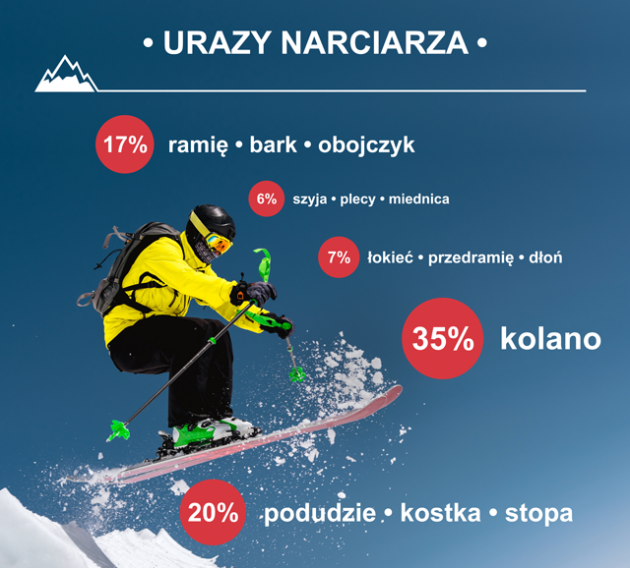

Urazy więzadeł kolana obejmują 1/3 wszystkich uszkodzeń stawu. Ze względu na duże ryzyko nadmiernego ruchu skrętnego stawu, najbardziej narażonym na uszkodzenia więzadłem narciarza jest więzadło poboczne piszczelowe (MCL). Oczywiście, na stoku niewiele rzadziej można doznać kontuzji i zerwania więzadła krzyżowego przedniego (ACL). Przewagę pod względem częstotliwości występowania urazu kolana u narciarzy, względem pozostałych części ciała, przedstawia poniższa grafika: Dlaczego kolano jest tak wysoce narażone na uszkodzenia w trakcie zimowego szusowania? Przede wszystkim, ze względu na strój narciarza i snowboardzista.

Buty narciarskie i snowboardowe doskonale zabezpieczają staw skokowy przed urazem w trakcie zimowych aktywności, natomiast w żaden sposób nie ochronią kolana. Co więcej, unieruchomienie i całkowite zabezpieczenie stawu skokowego i podudzia powoduje podwójną kumulację sił działających na staw kolanowy.